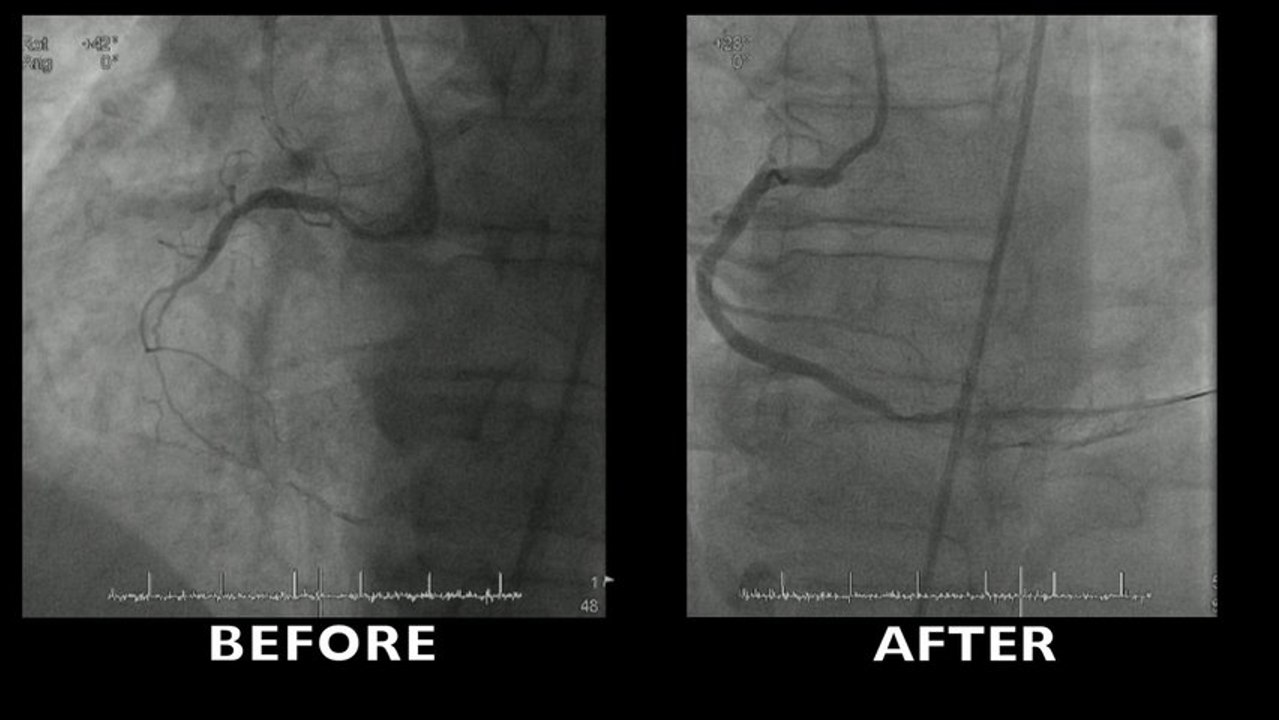

Description of lesion

• Long occlusion of mid LAD

• Length > 20mm

• Calcification

• Entry point: blunt stump

• Retry

• JCTO score 4

Description of procedure

• Bilateral approach, left and right radial

• Antegrade failure with fine cross and wire escalation (Fielde XT, Ultimate and Gaia 2

• Retrograde approach with corsair

• Retrograde crossing with Gaia 2 and Corsair

• Need for septal pre-dilatation

• Need for creating a shorter guide

• Need for mother and child technique

• Position loose

• Antegrade crossing with Gaia 2 using the retrograde channel created with Corsair

• Undilatable lesion and need for laser